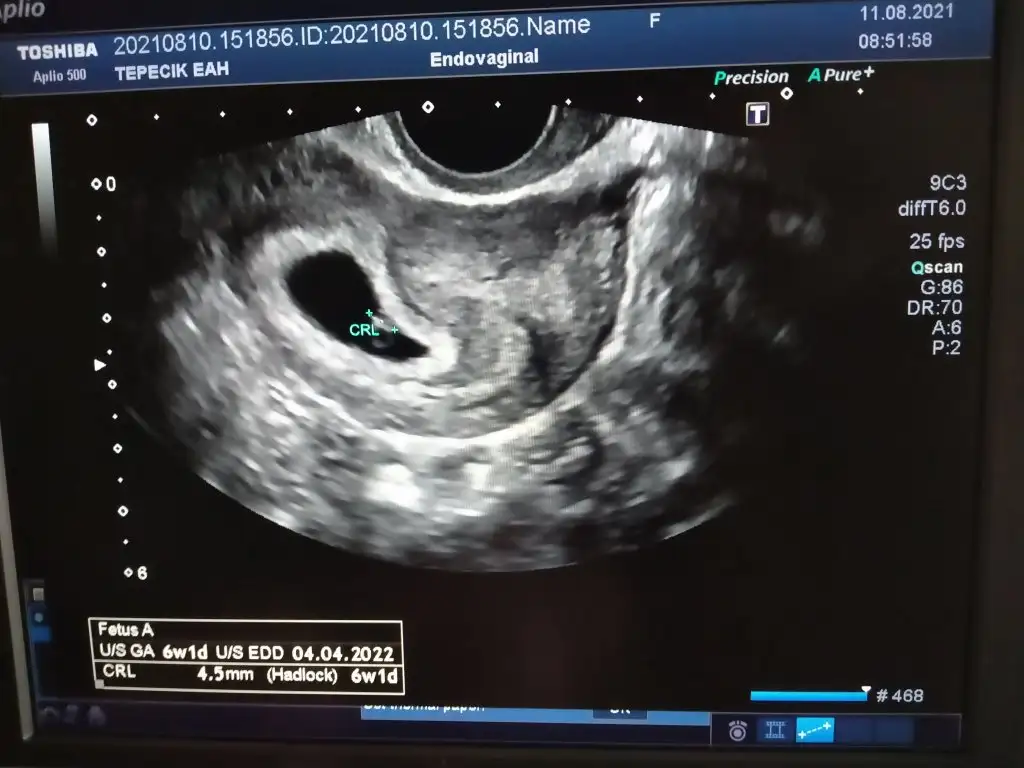

Kız gibiBenimkinede bakabilirmisiniz karından 7 haftalık

Merhaba banada baka bilir misiniz 7+4 karındanKız gibi

Kız gibi seninki de canım. Ramzi teorisine göre karından embriyo sağdaysa kız, soldaysa erkekmiş. En doğrusunu doktor bilir amaMerhaba banada baka bilir misiniz 7+4 karından

Ramzi teorisine göre cinsiyet tahmini yapacagim ilk ultrasyon resminizi atin bakiyim. Eger cinsiyetiniz belliyse hic söylemeeyin bakalm dogru tahmin edebilecekmiyim daha dogrusu ramzi teorisi hakli cikacak mi?